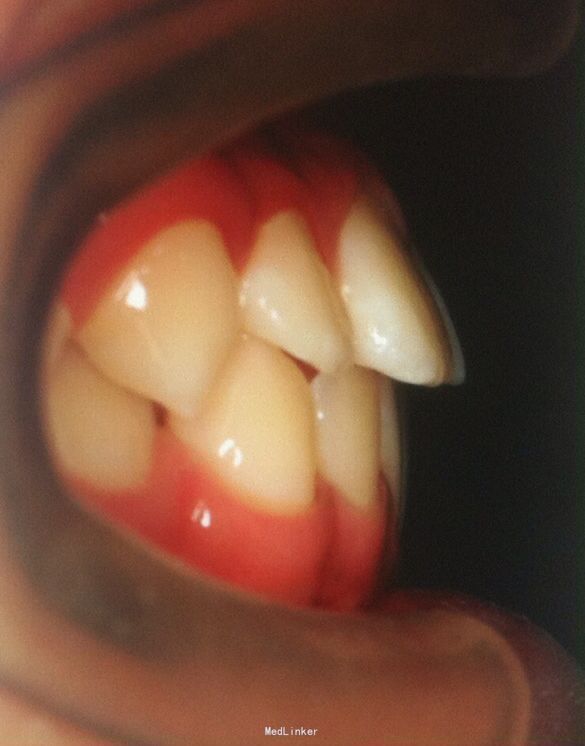

恒牙期 磨牙中性关系 前牙覆合覆盖关系正常 A1B1之间1mm间隙

安氏一类 不拔牙矫治,直丝弓矫治器,排齐整平上下牙列,关闭前牙散在间隙,矫治后磨牙中性关系,前牙正常覆合覆盖,维持现有面型